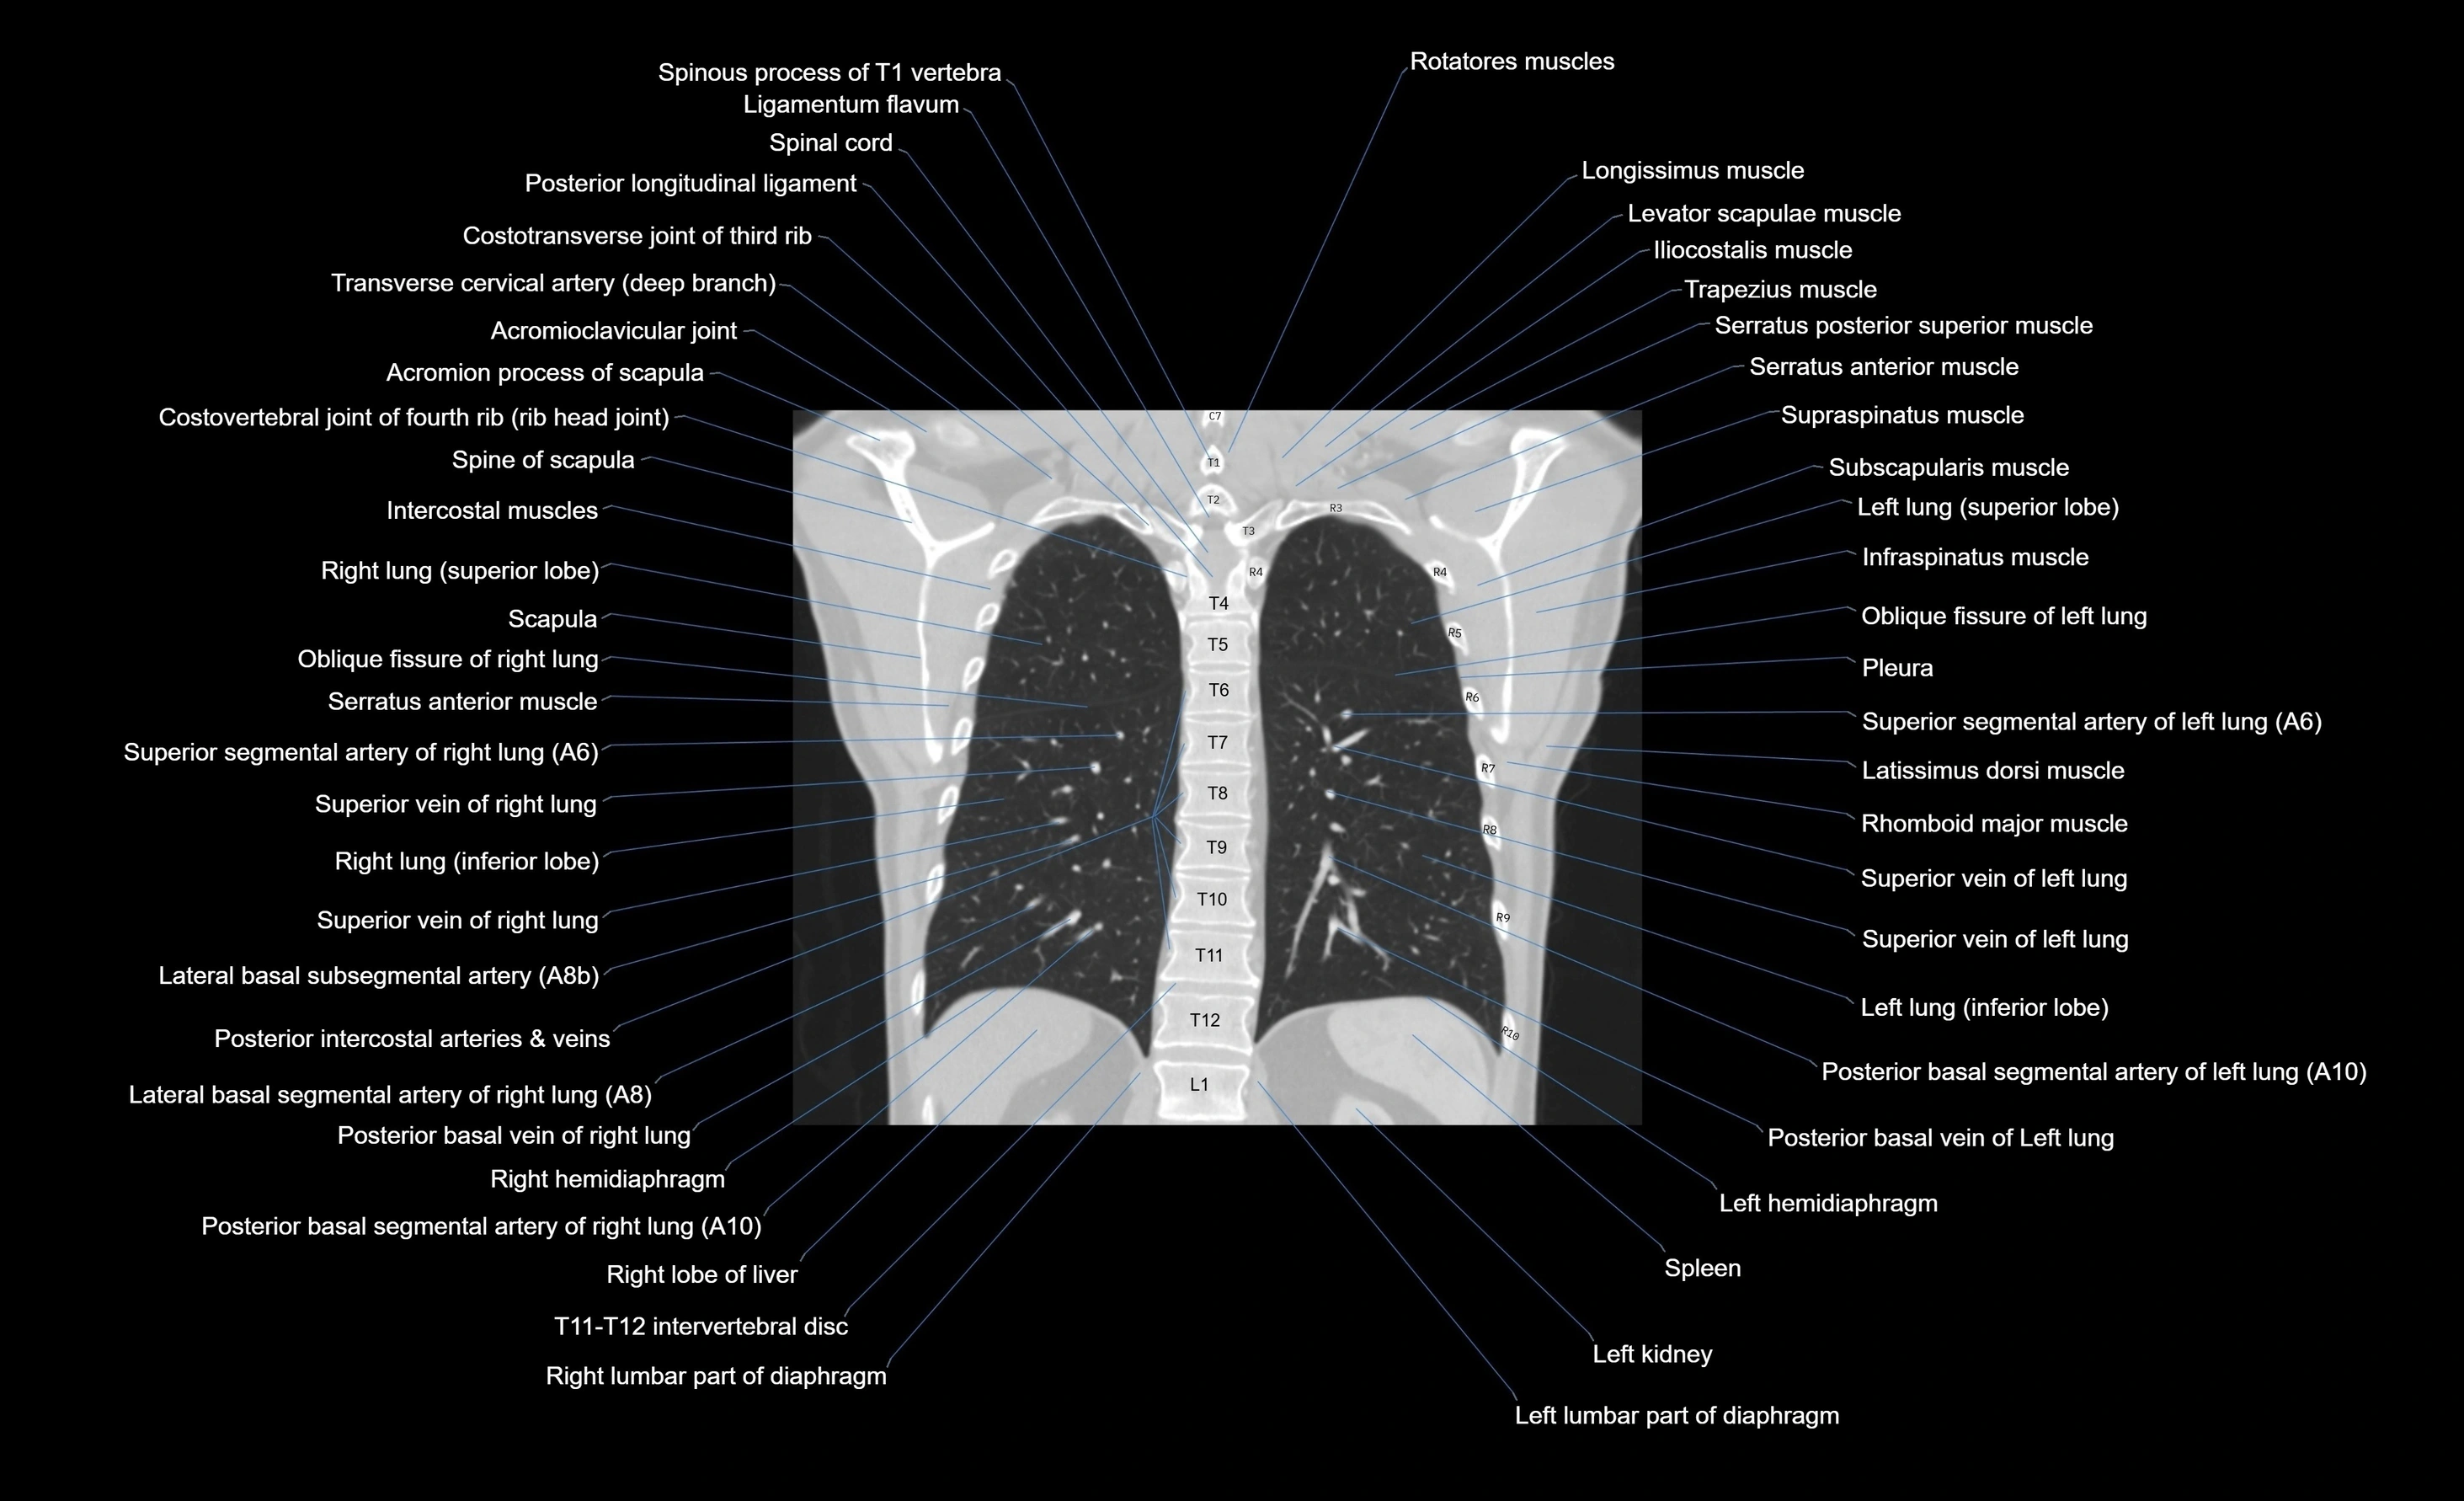

CT images